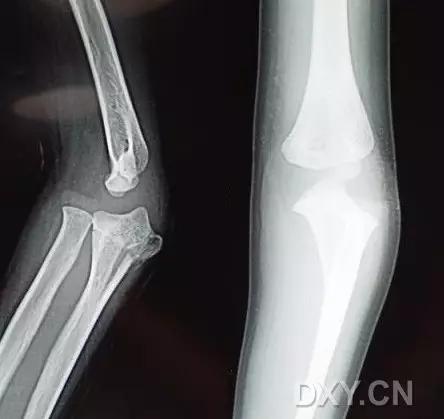

9. Monteggia 骨折(孟氏骨折)

尺骨近端 1/3 骨折合并桡骨头半脱位。

(来源:Radiopaedia)

成人 Monteggia 骨折

儿童 Monteggia 骨折